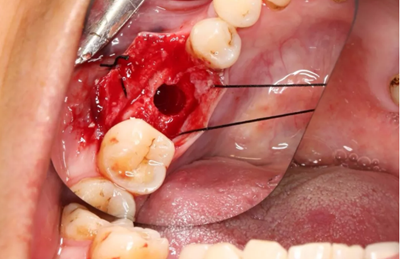

12、延期種植手術(shù)過程

使用直徑3mm的環(huán)形取骨鉆切取長約9mm的柱狀骨標(biāo)本,用于組織學(xué)和顯微影像檢查

(攝于2017年4月14日)

由于取骨致窩洞較大,加之缺牙間隙大,只好選擇植入5mm直徑種植體;種植備洞完成后,頰側(cè)骨壁厚度僅約1mm。